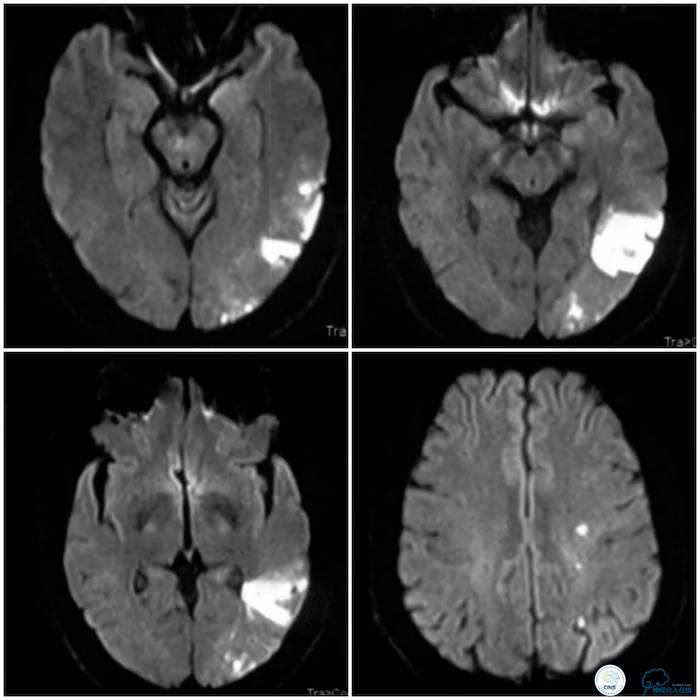

患者,男性,50岁,主因“右侧肢体无力伴言语不利2个月”入院。患者2个月前无明显诱因出现右侧肢体无力,表现为右上肢持物欠稳,右下肢行走拖曳,伴命名性失语,肢体无力持续约5分钟好转,但仍有言语笨拙。至当地医院就诊,查头颅MR示左侧颞枕分水岭区脑梗死(图1)。

图1

予“拜阿司匹林、氯吡格雷、阿托伐他汀”,治疗症状好转出院。2周前患者症状反复,再次到当地医院就诊,复查头颅MRI示左侧基底节区、放射冠、半卵圆中心、顶叶多发急性脑梗死(图3)。

图3